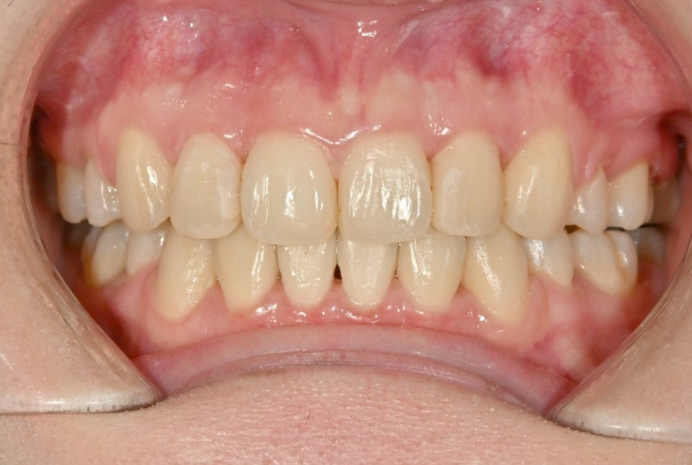

이제 전후비교 보겠습니다.

총 치료기간은 2년 2개월, 재제작은 1회 했습니다.

23.07~25.09

유지장치까지 들어간 모습이죠.

거미스마일은 완전히 해소되었으며 스마일라인와 입동굴은 적절합니다.

예쁜 앞니 각도가 돋보이네요.